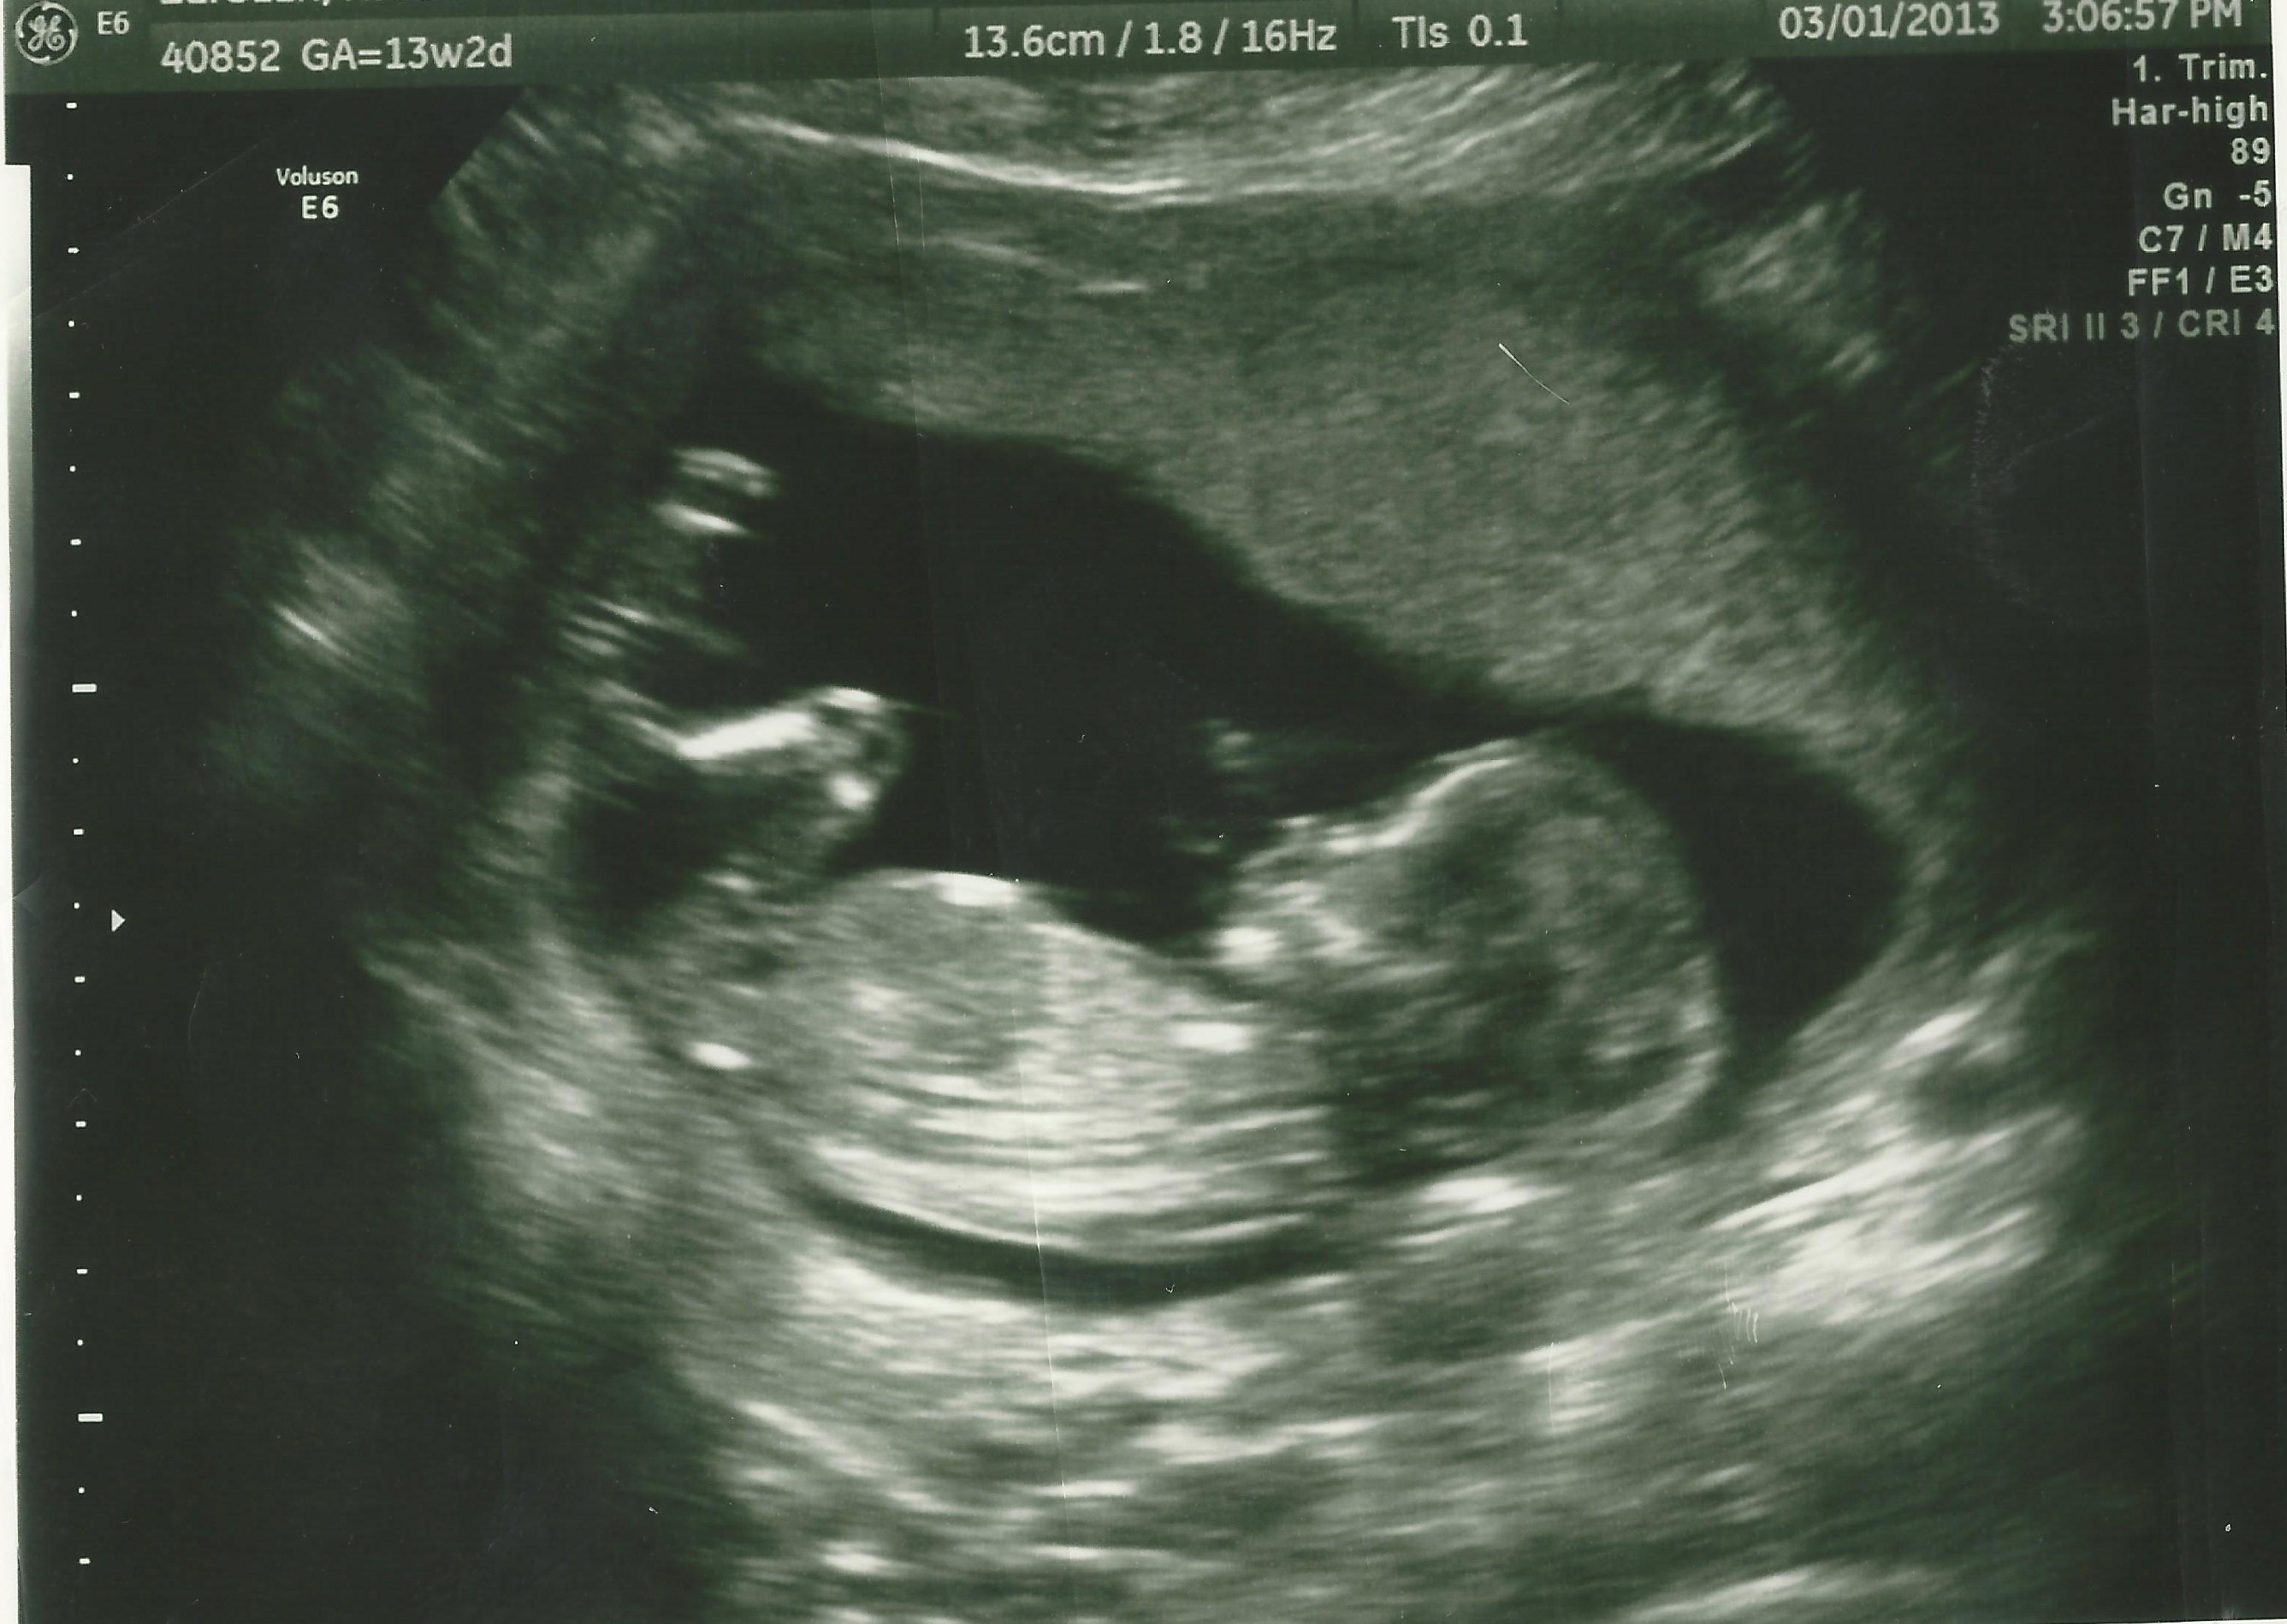

What Does Nt Mean On Dating Scan / normal 1st trimester ultrasound how to : The scan is usually performed transabdominally but in a few cases it may be necessary to do the examination transvaginally.. And yet, bizarrely, after your dating scan at 12 weeks, your due date can get less accurate the more pregnant you get. 4 when a scan shows a nuchal translucency (nt) measurement of 3.5millimetres or more information for parents definitions nuchal translucency (nt) scan you will have an nt scan when you are between 11 weeks and 2 days and 14 weeks and 1 day pregnant. Nuchal translucency refers to the sonographic image showing the fluid accumulation behind the fetus' neck. The scan is usually performed transabdominally but in a few cases it may be necessary to do the examination transvaginally. A dating scan shouldn't hurt, but sometimes the sonographer does have to press quite hard on your tummy, which can be a bit uncomfortable, and may leave you with a few bruises.

The nuchal translucency scan is done between 11 and 14 weeks of pregnancy. The size of the baby correlates less and less with its age as time goes on. It helps doctors determine if a baby is statistically more likely to have a chromosomal abnormality. This scan can work out the due date and gestational age of the baby, if you're having more than one baby and also screen for conditions like down syndrome. Nuchal translucency (nt) measurement nuchal translucensy (nt) is the clear space in the tissue of your developing baby's neck.